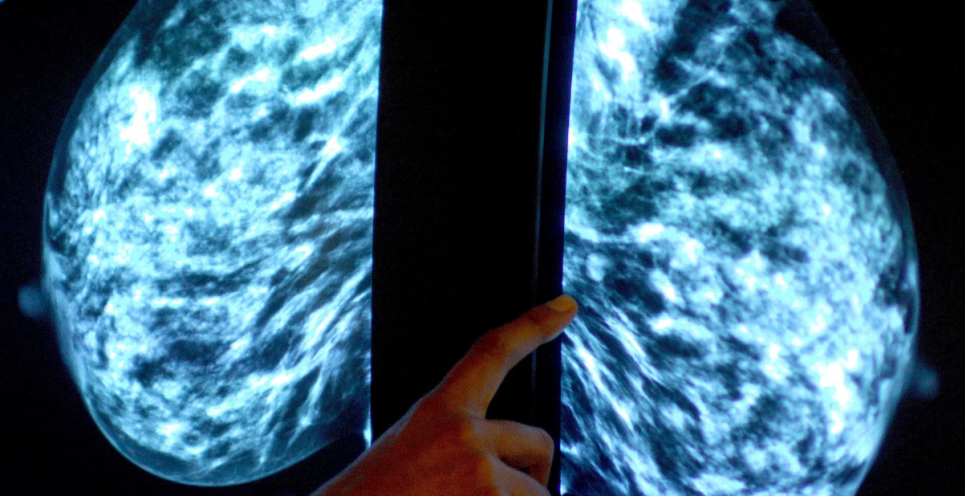

За даними Europe Cancer Patient Coalition (ECPC), рак молочної залози залишається найпоширенішим онкологічним захворюванням серед жінок Європи і є провідною причиною смертності від раку у жіночій популяції.

Приблизно 1 з 8 жінок протягом життя зіштовхнеться з діагнозом раку молочної залози.